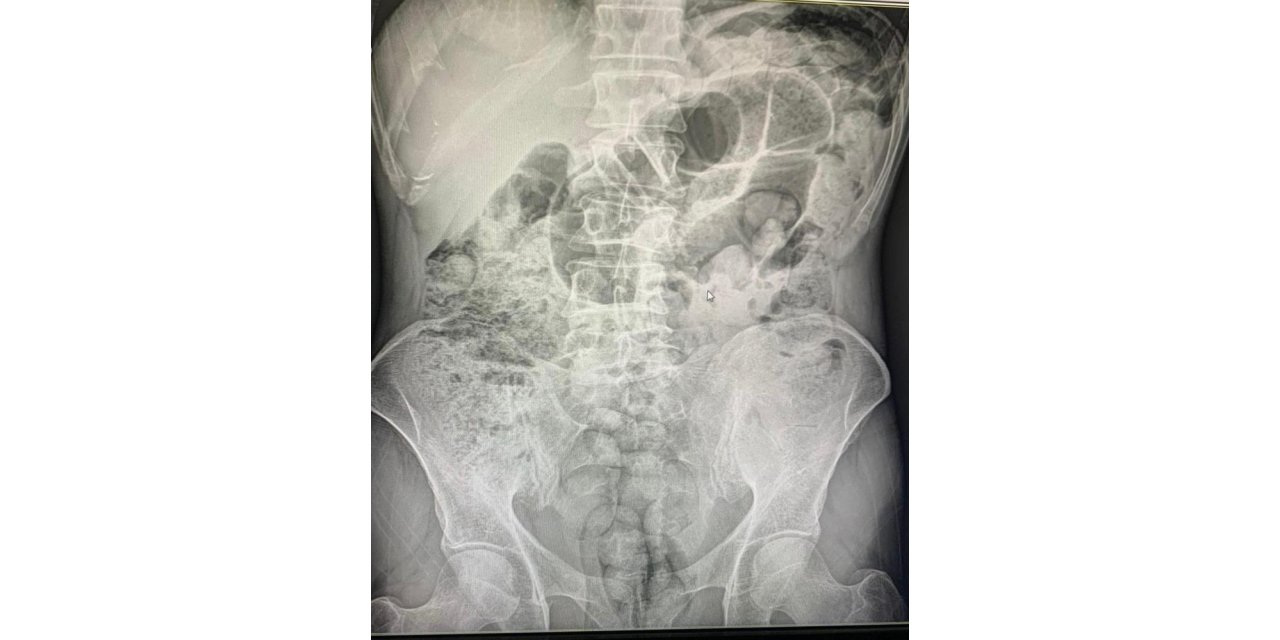

Siirt'te 4 zanlının midelerindeki 1 kilo 597 gram uyuşturucu madde, 10 günlük hastane sürecinin ardından cerrahi müdahaleyle çıkartıldı. Zanlılar çıkarıldıkları mahkemece tutuklandı.